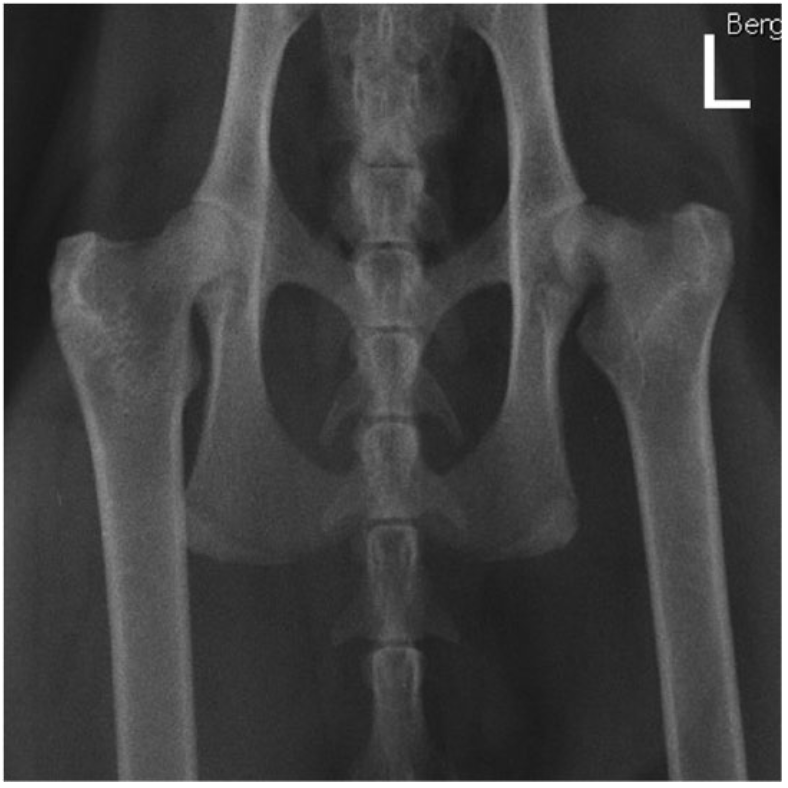

X光是最主要用來診斷這個疾病的影像工具。疾病的初期的X光影像呈現未關閉且變粗的生長板,並且可能伴隨很微小的股骨頭位移。隨著疾病的發展,股骨頭的錯位會越來越明顯,股骨頸的地方可能也會出現嚴重的骨吸收。此外,患有這個疾病的貓咪其他地方的生長板也常看到延遲關閉的狀況。

很重要的是,在診斷這個疾病時,可能要拍很多張不同姿勢的X光以提高診斷率。尤其是『蛙腿姿』的X光片,這個姿勢可以讓關節囊放鬆,比較不會因為緊繃的關節囊造成滑脫處復位而使得錯位處變得不明顯。